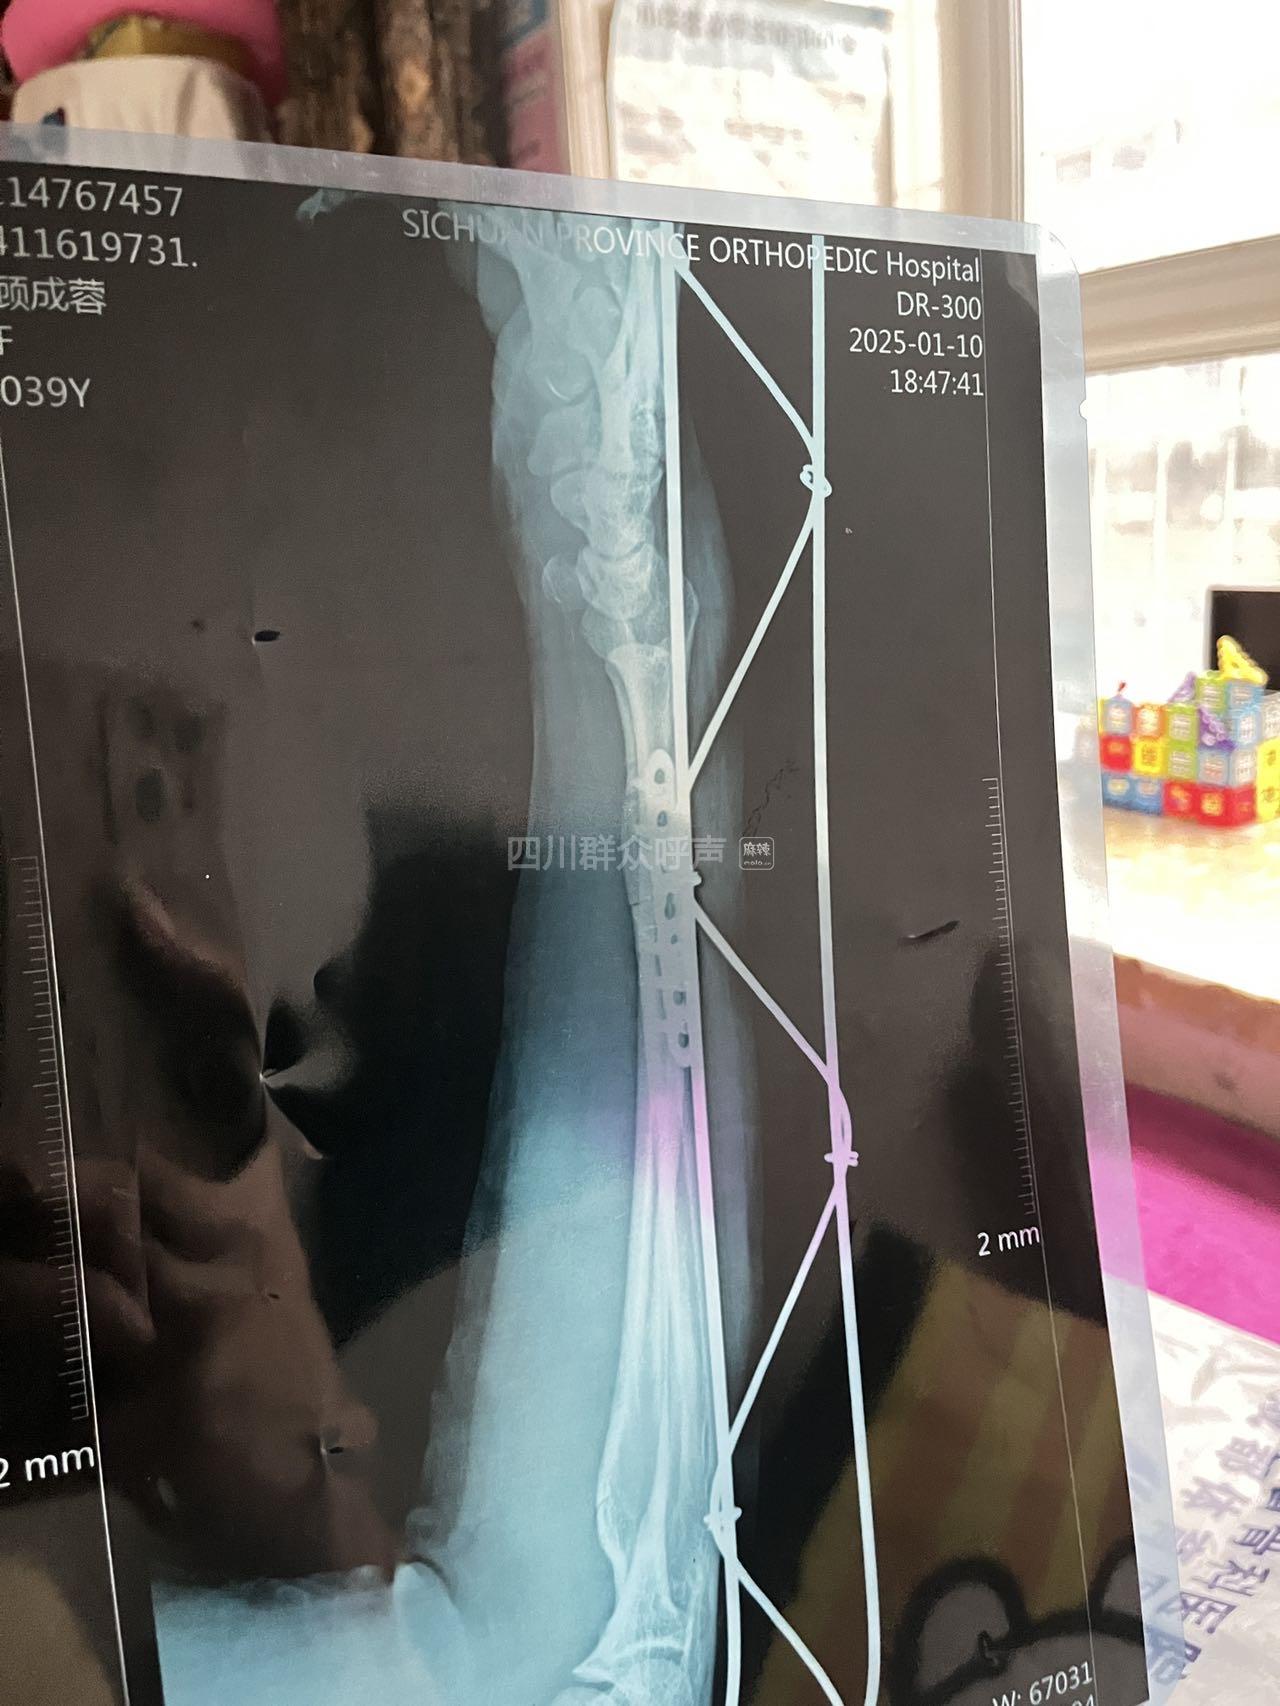

被故意伤害 已办结 求助

[求助] 被故意伤害